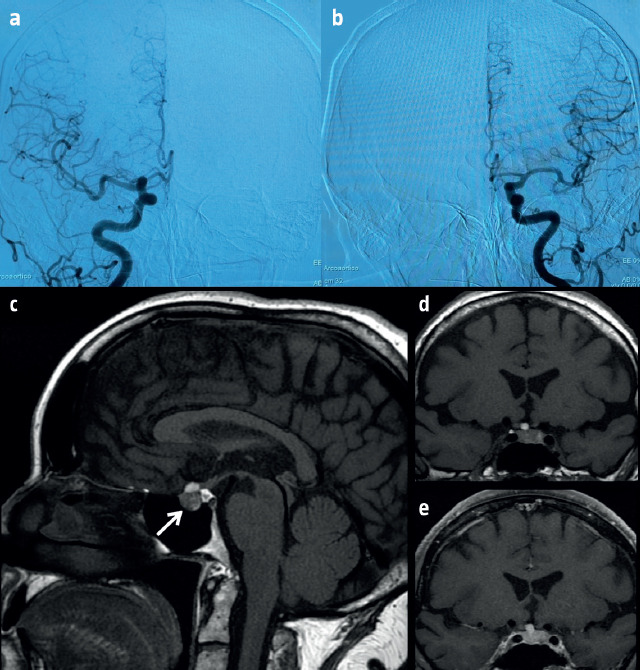

Hemorrhagic adenoma mimicking anterior communicating artery aneurysm.